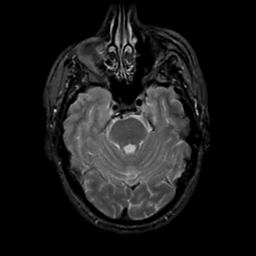

MR Study #20 October 6, 1991 -- Slice #15

[Home][Help][Clinical][Tour 1][Tour 2] Slice 15